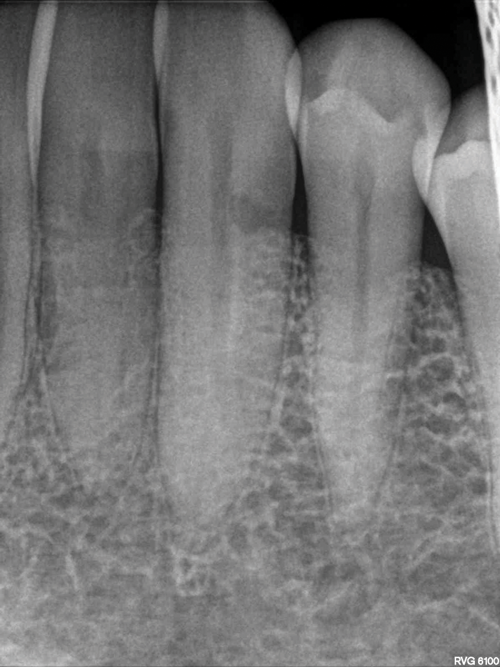

When using periapical radiographs in diagnosis, external resorptive defects should appear to move when captured from differing angulations and will have a visible and intact pulp chamber in all but advanced cases.1 All radiographic findings can help to differentiate ECR lesions from internal root resorption lesions, which have symmetrical, smooth, and clearly defined walls that appear to balloon out from the pulp chamber and do not appear to move with multiple parallax images. Conversely, ECR lesions have a less defined, irregular, and "ragged" or "moth-eaten" appearance and demonstrate variations in density, which makes them distinct from internal root resorption lesions that are usually uniform in density (Figure 7).2,14

On radiographs, early ECR lesions may exhibit a diminutive spot at the cementoenamel junction (CEJ), which may be confused with cervical burnout, but throughout the majority of the lesion, the root canal should be visible and intact. Advanced ECR lesions will appear as large radiolucent areas with less well-defined or "moth-eaten" borders that can extend into the pulp space.25 If an ECR lesion is in the repair-remodeling stage of development, it may appear more radiopaque due to the ossification of granulation tissue. Radiopaque spots may also be observed due to disruption of the PRRS that has led to local calcification of pulp tissue.6